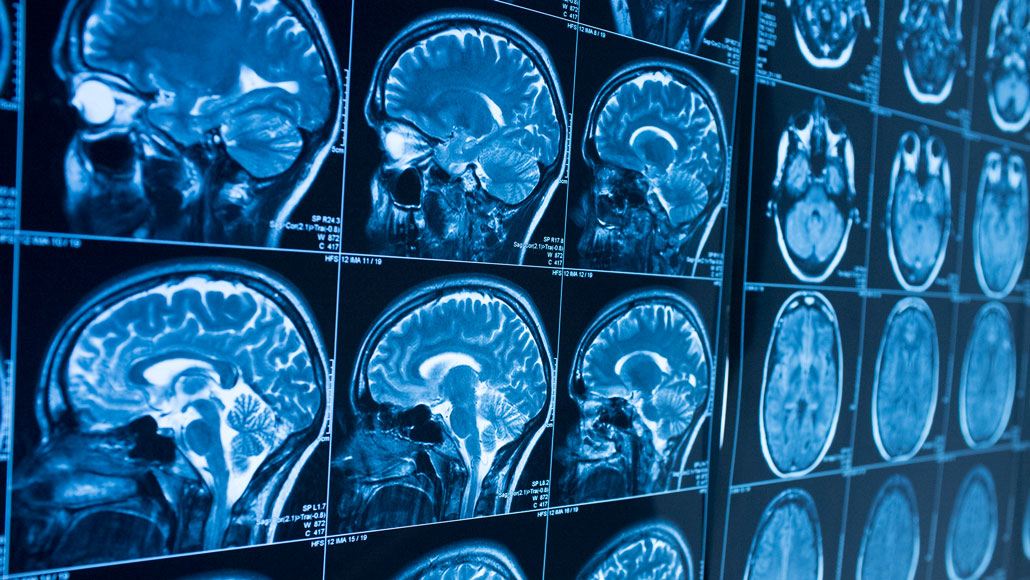

ALTOGETHER NOW  Fast ripples of activity appear in the hippocampus, a memory center in the brain, right before a person describes a previously seen image, a study finds.

Movus/iStock/Getty Images Plus